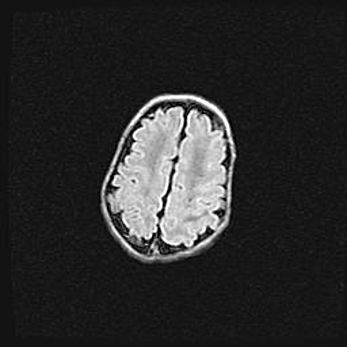

Неполная лизэнцефалия (пахигирия). Открытая гидроцефалия.

Возраст: 17 дней

Вес: 3110 г

Пол: мужской

Окружность головы: 33,5 см

Срок гестации: 35-36 недель

Лизэнцефалия—недоразвитие корковой пластинки и мозговых извилин в результате нарушения миграции нейронов коры. Поверхность мозговых полушарий гладкая. Микроскопически выявляется отсутствие нормальных слоев коры и скопление групп нейронов в подкорковом белом веществе.

Пахигирия—уменьшение числа вторичных извилин. В пораженном полушарии нервные клетки образуют толстый недифференцированный слой с неправильно расположенными нервными волокнами и группами гетеротопных клеток. Нервные клетки незрелые. Белое вещество истончено. При этом нередко аномально развит корково-спинномозговой путь.